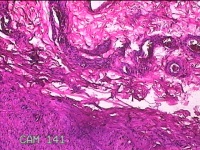

左侧手背结节

性别

男

年龄

43岁

临床诊断

皮下结节

一般病史

患者于近1个月来发现左侧手背一结节,伴局部隐痛不适,无发热。

标本名称

大体所见

灰白暗红色结节1.2x0.3x0.2cm一个,表面光滑。

疑似 :血栓形成。